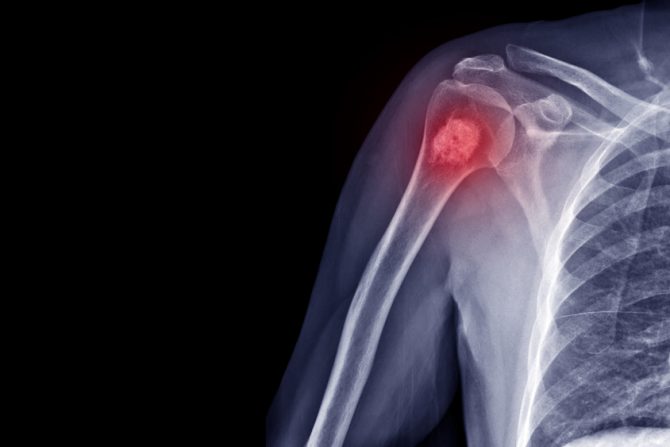

Nova metoda snimanja kostiju pruža hirurgu mogućnost da u trenutku dok operiše razlikuje zdravu od kancerogene kosti i tako sačuva što više zdravog koštanog tkiva

Rak kostiju ubuduće će se lečiti novom dijagnostičkom tehnologijom - laserskim svetlom koje će moći da sačuva veliki deo kosti, saopštili su istraživači sa Nova metoda snima kosti tako da hirurg za samo 11 minuta dobija preciznu sliku koja ukazuje koji deo kosti je zdrav a koji kancerogezan, a detalji nove tehnologije objavljeni su u Nature Biomedical Engineering.

Ovo je posebno problematično kada pacijent boluje od raka kostiju. Kosti predstavljaju jedinstvene izazove tokom operacije zbog toga što su čvrste u poređenju sa drugim tkivima i zato što rastu mnogo sporije od drugih vrsta tkiva.